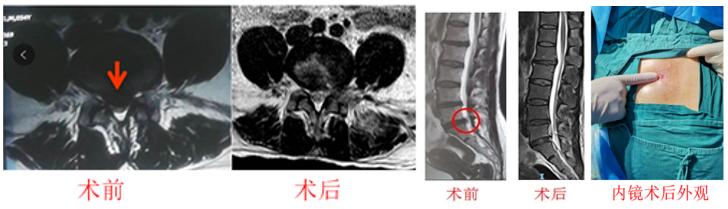

2. 经皮内镜下腰椎椎管减压术是治疗腰椎间盘突出症、腰椎管狭窄症的安全、有效的微创术式,经过江晓兵教授的改良优化后,手术可高效、安全完成,效果优于开放手术、显微镜或显微内窥镜下腰椎间盘切除术,而且非常微创,术后当天或1天即可出院、切口只需要7毫米左右、术后1周内即可恢复工作。目前,已能够全面覆盖各种严重椎管狭窄及骨性压迫的腰椎病,部分腰椎滑脱也可以通过内镜来治疗。

真正诠释了我们的宗旨:能孔镜不融合!